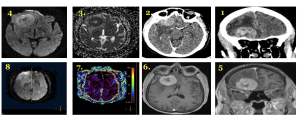

ממצאים הדמייתים

- CT עם וללא ח״נ (תמונות 1-2) - hyperdense ± דימום, נקרוזה. לרוב האדרה הומוגנית.

- T1WIC+ (תמונות 5-6) - היפראינטנסי הומוגני ברובו.

- DWI (תמונה 3-4) - רסטריקציה עם ADC ↓.

- PWI (תמונה 7) - rCBV ↓.

- SWI (תמונה 8)